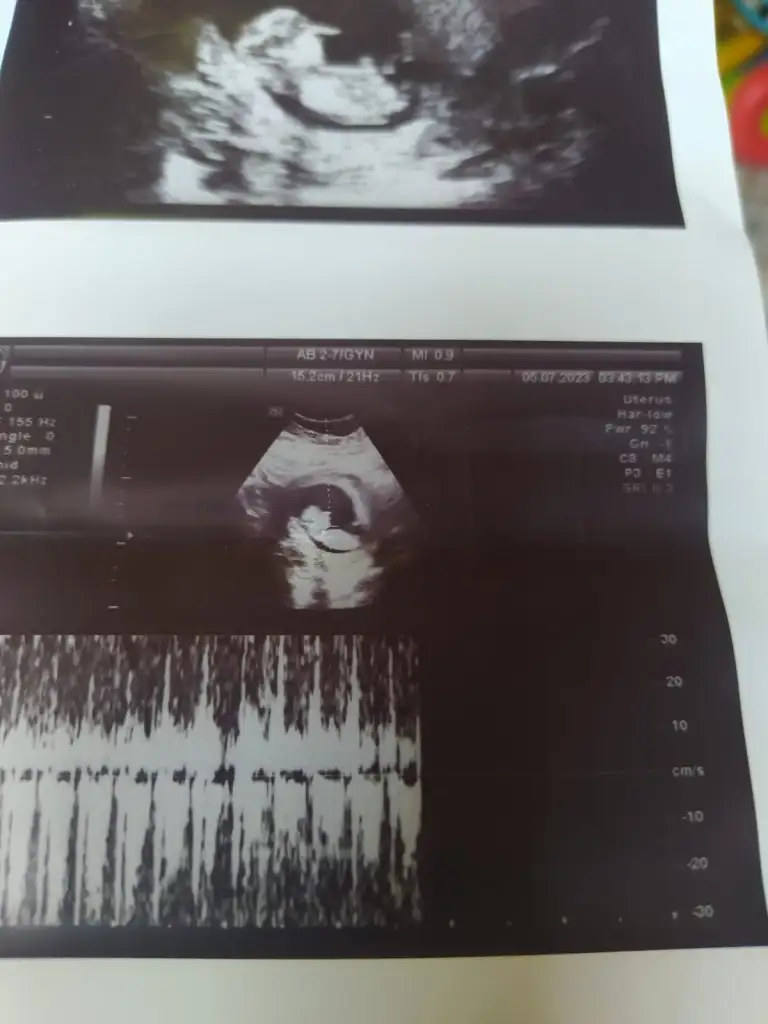

Selam arkadaşlar buraya bir arkadaşmn ultrason fotoğrafları atıyorum bir türlü cinsiyet oğrenemedi çok merak ediyor sizden ricam bir tahminde bulunabilirmsnz soyasosu canm sen anlıyordun dmi

• IMG-20230717-WA0006.webp

IMG-20230717-WA0006.webp

20,9 KB · Görüntüleme: 75

• IMG-20230717-WA0005.webp

IMG-20230717-WA0005.webp

19,6 KB · Görüntüleme: 77

• IMG-20230717-WA0004.webp

IMG-20230717-WA0004.webp

21,7 KB · Görüntüleme: 70